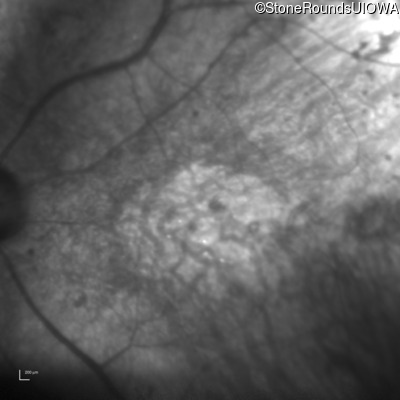

Infrared Fundus Photograph - Right - Hand Motion sc

Exemplar